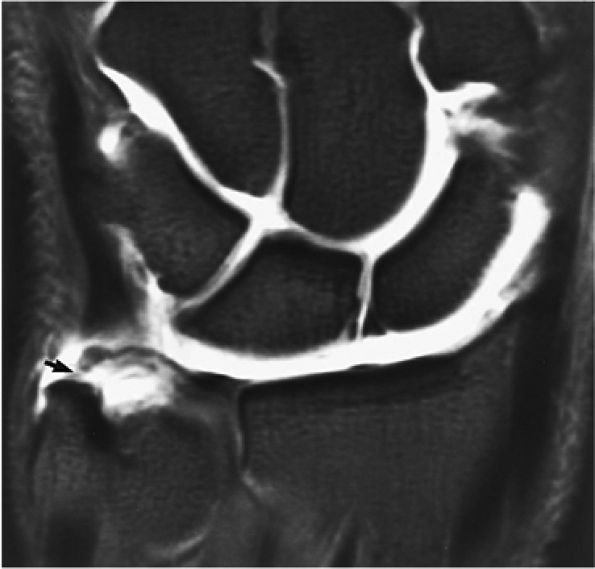

FIGURE 10.1 ● A 3D fast spoiled GRASS (FSPGR) with intra-articular contrast injected into the radiocarpal compartment. The torn lunotriquetral ligament (straight arrow) allows extension of contrast into the midcarpal compartment and the torn radial attachment of the TFC (curved arrow) directs contrast into the distal radioulnar joint. Note the superior trabecular bone detail on this image (coronal image; TR, 40.4 msec; TE, 14.5 msec; FOV, 4 cm; slice thickness, 2.0 mm; matrix, 512 × 256; flip angle, 30°).